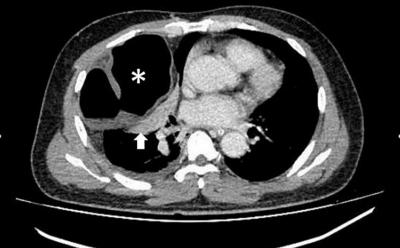

CT in axial view at the level of thorax with evidence of herniated bowel loop into the right thoracic cavity (*) complicated with collapse consolidation of the adjacent lung (arrow)

Diaphragmatic hernia

intestinal obstruction

multislice computed tomography